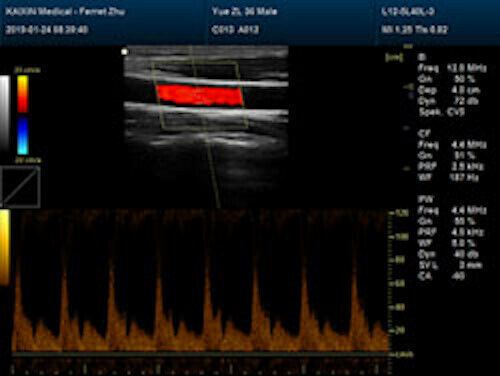

Save $ 1,079.82

DIAGNOSTIC ULTRASOUND MACHINES FOR SALE

Affordable Large Animal Veterinary Color Doppler Ultrasound & Rectal Probe

Sale price$ 4,919.18

Regular price$ 5,999.00